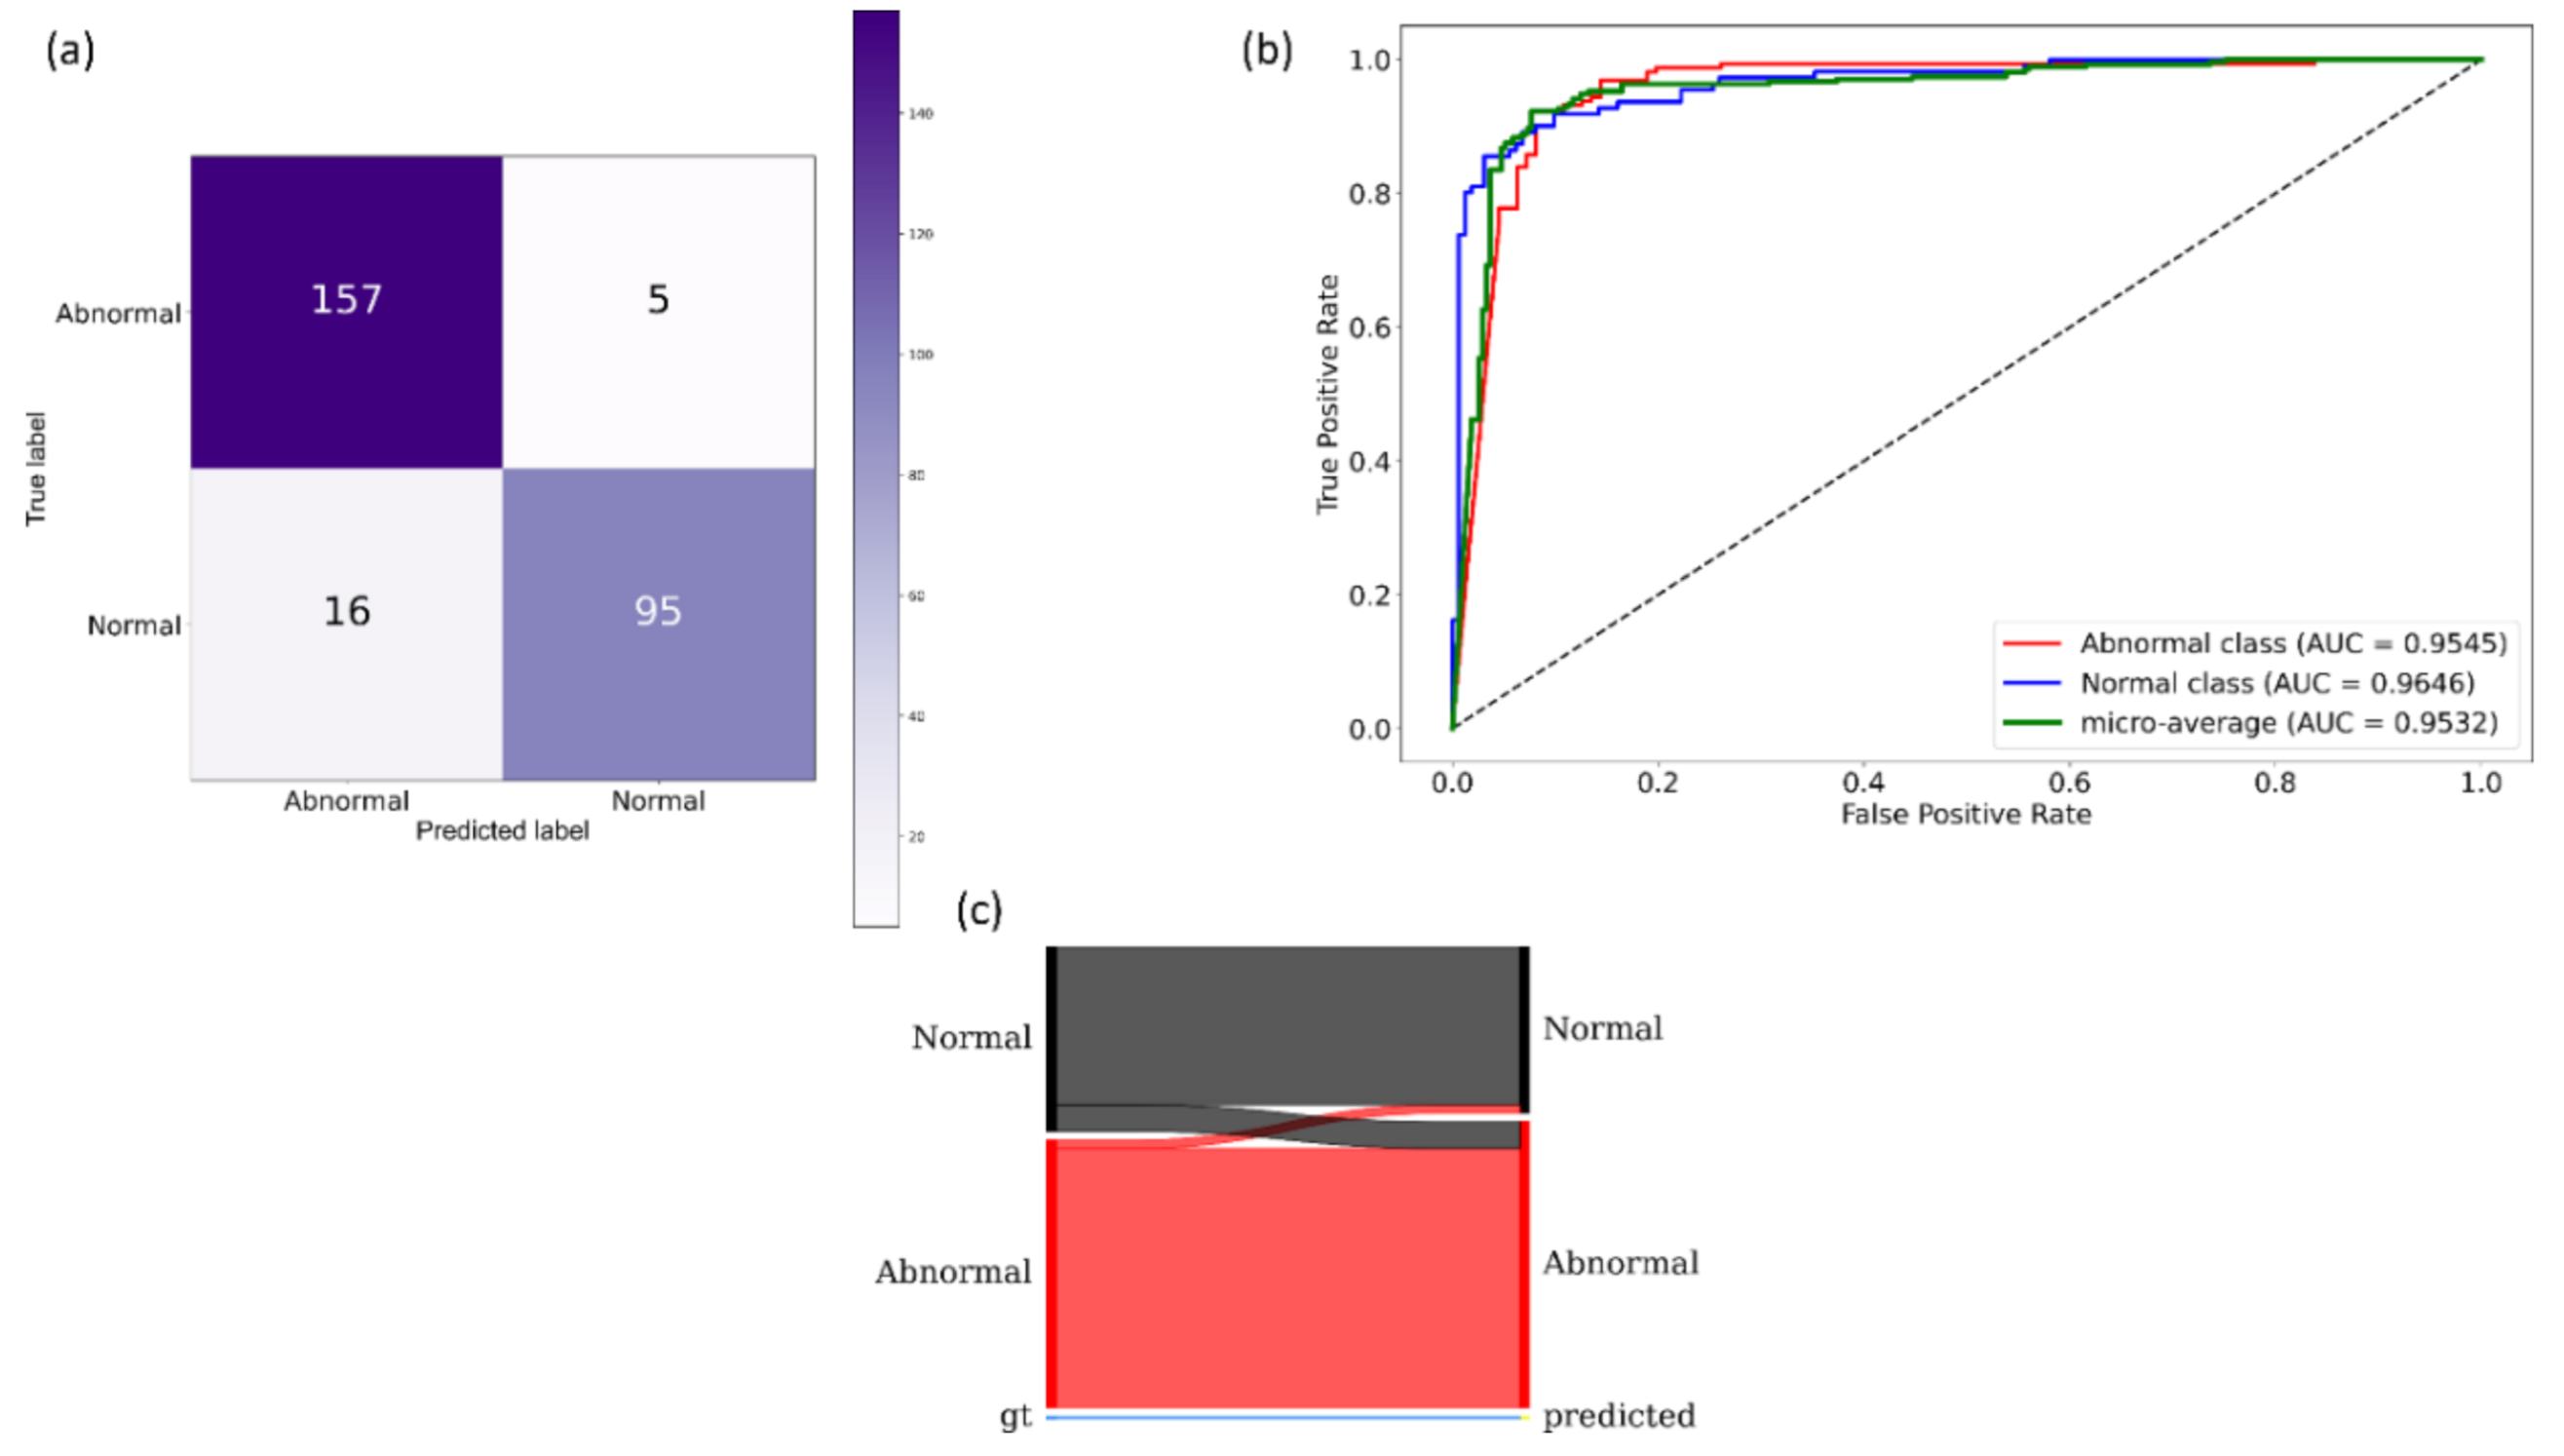

2.5. Model Fine-Tuning and Weak TB-Consistent Localization

The process workflow toward CXR modality-specific pretraining and fine-tuning is illustrated in

Figure 5.

The CXR modality-specific pretrained models are truncated at their deepest convolutional layer and appended with the following task-specific layers: (i) GAP, (ii) dropout (empirically determined ratio = 0.5), and (iii) dense layer with two neurons. The resulting models are fine-tuned using the lung-segmented, combined TB CXR collection, including India TB CXR, Belarus TB CXR, and Shenzhen TB CXR-Subset-1 datasets to classify them as showing normal lungs or pulmonary TB manifestations. The best-performing model from

Section 2.4 is used to segment the lungs in this collection.

During this training step, the combined TB CXR collection is split at the patient-level into 80% for training and 20% for testing. We allocated 10% of the training data toward validation with a fixed seed value. The performance of these fine-tuned models is compared to their baseline counterparts, i.e., the out-of-the-box ImageNet-pretrained CNNs that are fine-tuned on this collection. The models are optimized using the SGD algorithm to minimize the categorical cross-entropy loss toward this classification task. We used callbacks to check the internal states of the fine-tuned models.

The following metrics are used to evaluate models’ performance during CXR modality-specific pretraining and fine-tuning stages: (a) accuracy; (b) AUC; (c) sensitivity; (d) precision; (e) specificity; (f) F-measure; (g) Matthews correlation coefficient (MCC); and (h) diagnostic odds ratio (DOR).